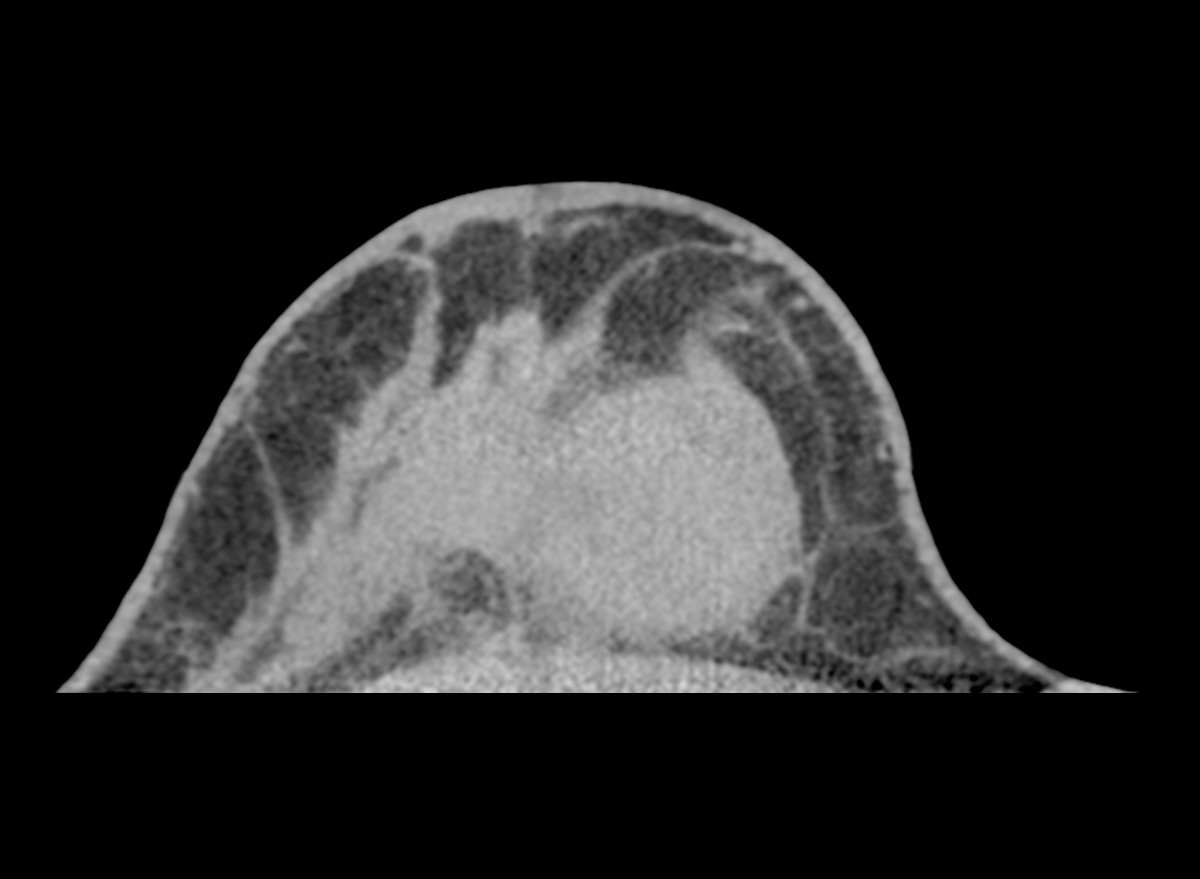

评估: BI-RADS 2

图片提供:Prof: Prof. Dr. med. Andreas Boss (USZ - 苏黎世大学医院)